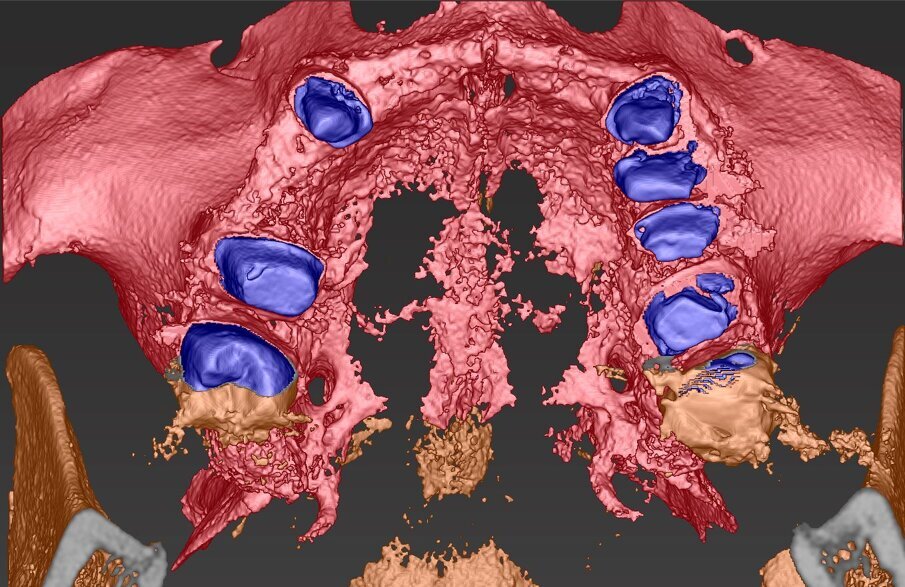

Per un’analisi completa in casi così compromessi è necessario il maggior numero di informazioni che dovranno essere raccolte partendo dal confronto con la paziente per quelle che sono le abitudini alimentari, la sua attività lavorativa, gli interessi sociali. Tutto ciò permette di capire quanto la paziente si aspetti dal nostro intervento ponendo la giusta attenzione all’estetica oltre che alla naturale funzione, è altresì importante rilevare delle immagini con e senza la protesi provvisoria in situ (Fig. 2). Nonostante si evinca la mancanza di congruità del manufatto protesico con la cresta residua la paziente ha mostrato difficoltà nel concepire una sua sostituzione per il timore di un peggioramento estetico. Il supporto di un progetto digitale ha consentito alla paziente di capire quale risultato potesse raggiungere a percorso ultimato. È evidente il collasso che il labbro superiore subisce quando viene rimossa la protesi con la rappresentazione del “codice a barra” dato dalla mancanza dei denti e della struttura ossea sottostante (Figg. 3, 4), a tal scopo è consigliabile poter fotografare la paziente nel profilo in entrambe le situazioni così da far emergere le discrepanze, anche nell’impronta digitale rilevata è importante acquisire il maggior numero di informazioni (Fig. 5). L’informazione diagnostica dettagliata è fornita dalla CBCT, pertanto abbiamo pianificato la sua esecuzione dopo la prima provvisorizzazione dell’arcata superiore evitando lo scattering da metalli presenti. Il file STL del wax-up (Fig. 6) associato al file STL dell’impronta senza provvisorio (Fig. 7) e al file DICOM radiologico (Figg. 8, 9) ha permesso una corretta progettazione chirurgico implantare (Fig. 10) nel rispetto della porzione ossea della cresta residua, ottimizzando la conseguente realizzazione della dima chirurgica (Fig. 11) per il posizionamento degli impianti in sede 1.2 e 2.2 (Figg. 12-14) anche nel rispetto della posizione degli elementi in antagonismo (Fig. 15).

Fig. 8_Impatto visivo della CBCT nella porzione vestibolare che evidenzia la marcata lacuna ossea che impatta sull’estetica del II° sestante.

Fig. 9_Nel taglio sagittale è possibile verificare la porzione ossea presente sull’intera arcata, si notano le preparazioni degli elementi naturali che faranno da link per la connessione nel progetto elaborato.

Fig. 10_La visione ingrandita del sito implantare esalta alcuni elementi che hanno contribuito nella scelta della posizione, dei materiali e della tecnica chirurgica esecutiva. Si nota Ion bianco il margine della dima chirurgica, in verde il profilo mucoso, in arancio la forma in sezione assiale della corona protesica in blu il contorno dell’impianto in Zirconia pure Ceramic e in giallo in tragitto di connessione che consentirà l’avvitamento della corona finale.